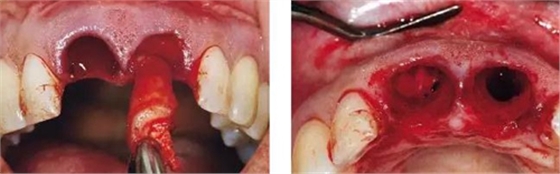

圖1、外形較大的雙側上中切牙唇側有瘺管,預后不佳,患者高笑線、薄齦生物型。

圖2、放射線片顯示雙側中切牙根尖均有感染病變。

圖3、微創(chuàng)小心拔除雙側中切牙,保護牙齦緣和齦乳頭不受損傷。

圖4、觸診檢查感知頰側有骨缺損,且瘺管與牙槽窩內肉芽組織相連。

圖5、左側用探針檢查可感知牙槽窩根方頰側軟硬組織的缺損??梢娧篱g乳頭很薄。

圖6、前庭溝半圓形切口,翻瓣后暴露左側和右側的骨缺損。

圖7、去除了肉芽組織和根尖感染組織,仔細沖洗后,可見雙側拔牙窩唇側骨壁有大面積缺損。